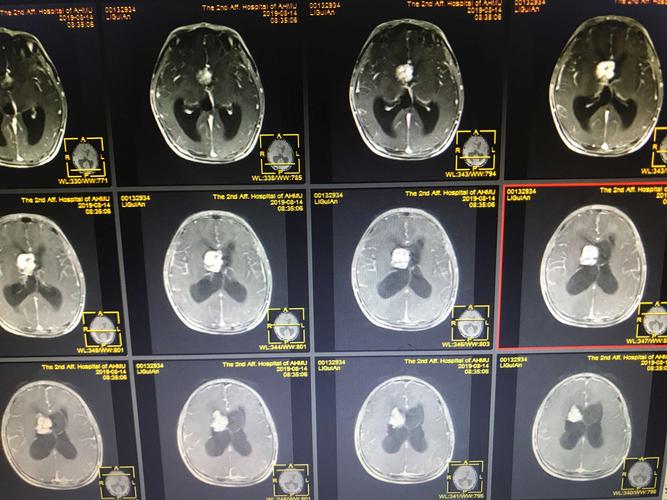

右侧侧脑室占位

侧脑室三角区肿瘤的诊断

侧脑室ct

侧脑室三角区

侧脑室ct图片